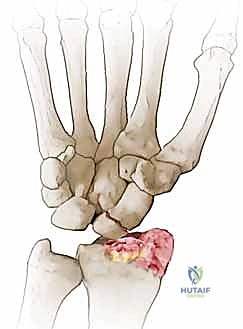

- المرحلة الأولى (Stage I): خشونة وتآكل في المفصل بين القطب البعيد للعظم الزورقي وعظم الكعبرة (الناتئ الإبري الكعبري).

- المرحلة الثانية (Stage II): يمتد التآكل والخشونة ليشمل المفصل الزورقي الكبير (Scaphocapitate joint).

- المرحلة الثالثة (Stage III): تدهور كامل يشمل المفصل بين عظم الهلالي والعظم الكبير (Capitolunate joint)، مع انهيار كامل لهيكل الرسغ.

تُعد عملية استئصال القطب البعيد للعظم الزورقي (Excision of the Distal Pole of the Scaphoid) حلاً جراحياً ذكياً ومبتكراً. الفكرة الميكانيكية وراء هذه الجراحة هي: "إذا كان القطب البعيد للعظم الزورقي هو الذي يحتك بعظم الكعبرة ويسبب الألم والخشونة، فلنقم بإزالته مع الحفاظ على باقي هياكل الرسغ".

- الاستئصال الدقيق: باستخدام أدوات جراحية ميكروسكوبية دقيقة، يتم استئصال حوالي 3 إلى 4 مليمترات من القطب البعيد للعظم الزورقي. هذه الكمية كافية لمنع الاحتكاك مع عظم الكعبرة، وفي نفس الوقت تحافظ على استقرار الأربطة.

في حال كانت الخشونة قد وصلت لمراحل متقدمة جداً (المرحلة الثالثة)، فإن استئصال القطب البعيد قد لا يكون كافياً. هنا تبرز خبرة البروفيسور هطيف في تقديم البدائل الجراحية المعقدة: